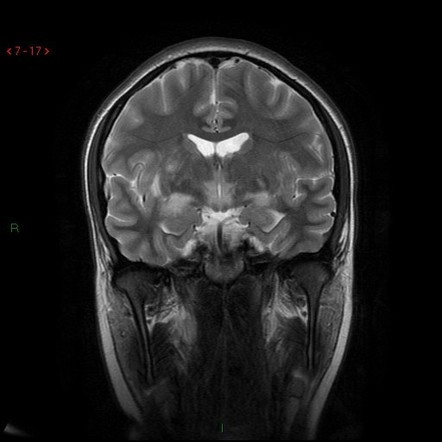

Sau nhiều năm nghiên cứu, các chuyên gia tìm ra căn bệnh khiến nhiều người trở thành "bức tượng sống". Đó là căn bệnh Encephalitis lethargica hay còn gọi là bệnh ngủ.

Theo các chuyên gia, những người mắc căn bệnh Encephalitis lethargica có những triệu chứng ban đầu là buồn ngủ và khó tỉnh dậy như bình thường.

Vi khuẩn trên bị đột biến, tác động đến hệ thống miễn dịch của con người và tấn công não bộ. Điều này khiến người bệnh dần rơi vào tình trạng "đông cứng như tượng".